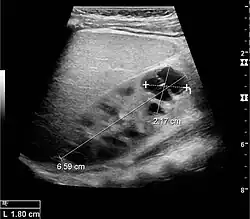

Figure 1. Normal adult kidney. Measurement of kidney length on the US image is illustrated by '+' and a dashed line. *Column of Bertin; ** pyramid; *** cortex; **** sinus.[1]

The length of the adult kidney is normally 10–12 cm, and the right kidney is often slightly longer than the left kidney. The adult kidney size is variable due to the correlation with body height and age; however, normograms for pediatric kidney size are available.[1]

Cortical thickness should be estimated from the base of the pyramid and is generally 7–10 mm. If the pyramids are difficult to differentiate, the parenchymal thickness can be measured instead and should be 15–20 mm (Figure 3). The echogenicity of the cortex decreases with age and is less echogenic than or equal to the liver and spleen at the same depth in individuals older than six months. In neonates and children up to six months of age, the cortex is more echogenic than the liver and spleen when compared at the same depth.[1]